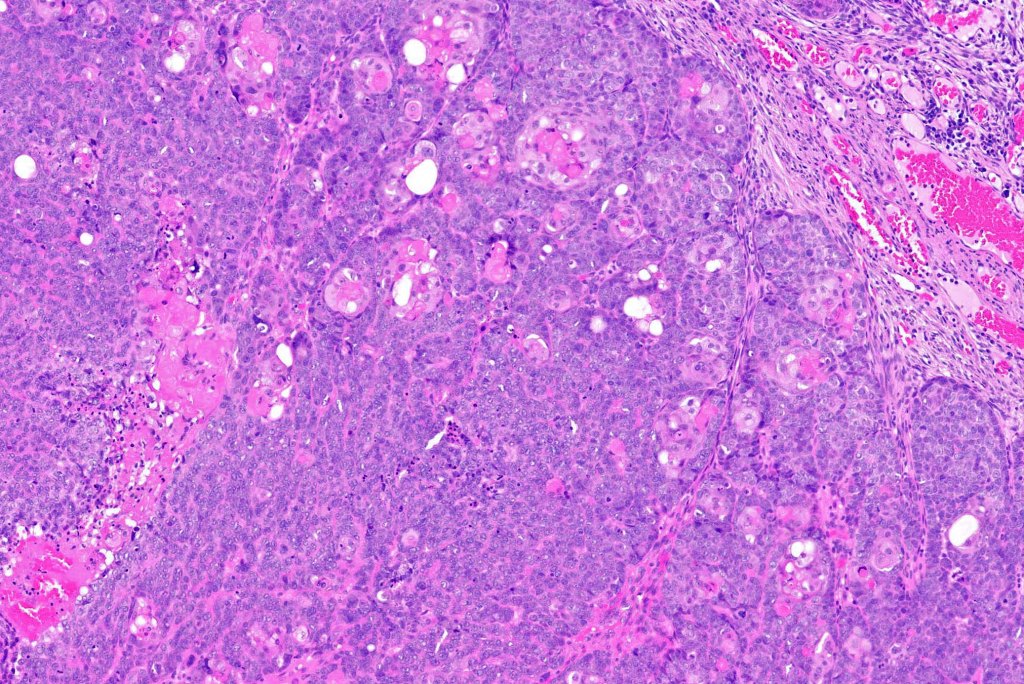

•Lobular or a diffusely infiltrating growth pattern. Composed of pleomorphic hyperchromatic, basaloid cells with nucleolar prominence, abundant mitoses & atypical mitoses (brisk mitotic activity should not be used as a defining feature of matrical carcinoma since in the evolving phase mitoses are typically very numerous in pilomatricoma)

•Necrosis common

•Matricial & supramatricial differentiation

•Clear cell change